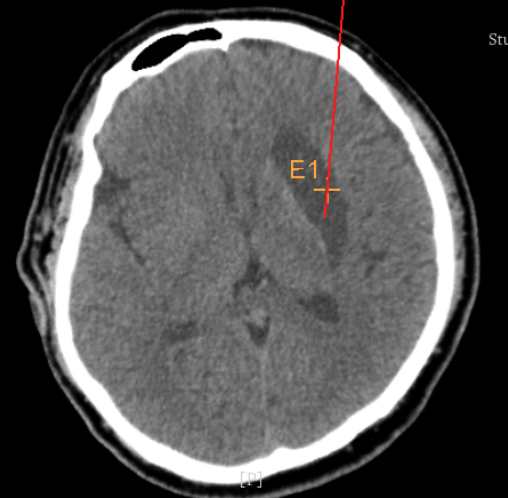

術(shù)前CT:血腫已經(jīng)液化,但仍有占位效應(yīng)

手術(shù)日當(dāng)天,醫(yī)生團(tuán)隊(duì)通過手術(shù)計(jì)劃系統(tǒng)為患者制定手術(shù)靶點(diǎn)及最安全的入顱路徑,隨后將手術(shù)規(guī)劃導(dǎo)入手術(shù)室的機(jī)器人當(dāng)中。

術(shù)前韓帥醫(yī)生使用“睿米”制定手術(shù)規(guī)劃

手術(shù)規(guī)劃在機(jī)器人軟件上制定完成